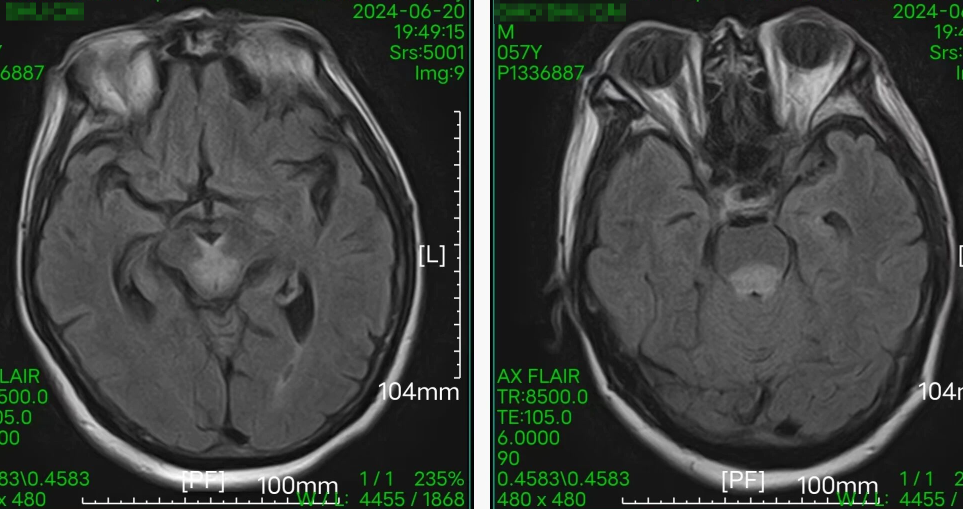

引言 生活中,很多人会突然出现“看东西重影”的情况,往往以为是眼睛疲劳或近视加深,并没有太当回事。然而,这背后可能隐藏着甲亢、脑梗、重症肌无力甚至肿瘤等十余种疾病的信号,是一个需要警惕的“隐形杀手”。 面对这类病因错综复杂的“复视”患者,市二院神经内二科赵智江主任带领团队,凭借丰富的临床经验和深厚的神经疾病诊疗功底,抽丝剥茧,多次成功揪出导致视物成双的“真凶”,为患者赢得了宝贵的治疗时机。 Part.01 复视背后,病因五花八门 神经内二科团队诊治了多位以“视物成双”为主诉的患者,其最终病因各异,充分体现了神经科疾病“同症异源”的复杂性。 以为是眼病,其实是甲亢 患者因复视就诊,经查双眼突出,影像检查发现控制眼球的肌肉异常肥厚。结合甲状腺功能检查,最终确诊为“甲亢性眼肌病”,其原因在甲状腺功能亢进的眼部表现。后经针对性纠正甲状腺功能,患者复视症状显著改善,眼外肌肥厚得到有效控制。 眼眶核磁 甲功结果 眼球状态 复视眼痛,原是痛性眼肌麻痹 患者右眼不仅看东西重影,还出现上睑下垂、眼痛等症状。团队排除其他可能后,诊断为痛性眼肌麻痹(Toloas-Hunt综合征),这是一种自身免疫性炎症。经治疗,患者眼睑下垂症状减轻,眼痛及复视基本消失,眼球运动范围显著恢复。 梅毒隐匿,损伤颅神经 患者因眼皮抬不起、眼球转动不灵并视物重影入院。常规血清检查发现梅毒抗体阳性,排除其它原因导致的复视,最终明确为“神经梅毒”侵蚀颅神经所致。确诊后立即给予驱梅治疗,效果明显,眼皮能抬起来了,重影消失了,眼球转动也灵活了。 糖尿病悄悄损伤神经 两位糖尿病患者,均以突发复视就诊。团队精准判断,发现分别是高血糖损伤了“动眼神经”和“外展神经”,属于糖尿病性单神经病变,表现为不同类型的复影(上下重影或水平重影)。明确诊断后,经严格控糖,辅以营养神经药物等综合对症治疗,患者病情好转,顺利出院。 脑梗“瞄准”不同区域 三位患者均因复视就诊,但伴随症状各异,有的行走不稳,有的走路右偏。赵智江主任团队通过精细的神经系统查体,精准定位于中脑的动眼神经核、桥脑的内侧纵束等。不同脑区梗死,复视的表现也完全不同。后通过溶栓药物、抗血小板药物、改善循环治疗等针对性治疗,辅以康复治疗,患者身体逐渐好转,出院时已无视物成双症状。 三位患者的核磁 典型信号——晨轻暮重 患者出现复视,伴言语不利、吞咽困难、饮水呛咳等症状。其中复视有个鲜明特点——早晨轻、傍晚重,疲劳后加重。经专项检查,确诊为“重症肌无力”(眼肌型)。这是一种神经肌肉接头疾病,免疫调节治疗可有效控制。经过一段时间的治疗,患者复视症状明显缓解,言语不清、吞咽困难症状得到显著改善。治疗前患者只能进食流食,治疗后可自主进食固体食物。 肿瘤病史者,需警惕转移 淋巴瘤患者在化疗期间出现复视和面瘫。团队通过脑脊液等深入检查,排除感染等因素,最终诊断为脑膜癌病。 嗜睡头晕,病因在营养 患者急性起病,表现为复视、头晕、嗜睡、走路不稳。团队结合其既往史和典型眼球活动障碍,迅速锁定病因——因维生素B1严重缺乏导致的“韦尼克脑病(Wernicke)”。补充维生素B1一周以后,患者复视症状改善、走路平稳、神志清楚,可独立行走。 Part.02 精准诊疗,揪出“元凶”是关键 赵智江主任指出:“复视只是一个临床症状,其背后可能是内分泌、炎症、代谢、脑血管、自身免疫、肿瘤等多种病因在神经系统上的投射,涉及学科广泛。” 市二院神经内二科团队通过详细追溯病史、进行一丝不苟的神经系统专科查体(尤其是眼球运动检查),初步判断病变可能位于动眼、滑车、外展神经的神经核团,神经及其所支配的肌肉、神经-肌肉接头等部位,然后精准选择并解读影像学、免疫学、生化及脑脊液等检查结果,最终整合信息,明确诊断,为患者制定出针对性的治疗方案。 市二院神经内二科在赵智江主任的带领下,始终致力于复杂疑难神经系统疾病的诊疗攻坚。科室凭借严谨的临床路径、对神经解剖与病理生理机制的深刻把握,以及精湛的诊疗技术,为众多罕见病与危重患者精准定位病因、制定个体化治疗方案,有效提升了救治成功率与患者长期生活质量。 提醒市民:如果突然出现视物重影,尤其是伴有眼皮下垂、眼球转动不灵、疼痛、头晕、行走不稳或其他神经系统症状时,切勿掉以轻心,应及时重视,这些症状有时可能与神经系统疾病相关。为了明确原因,获得更全面的评估,您可以考虑到神经内二科就诊,由专业医生进一步检查与诊断,以便尽早获得适合的照顾与治疗。 Part.03 人民医院 人民名医 赵智江 主任医师 副教授 ·葫芦岛市第二人民医院神经内二科主任 ·中国卒中学会高级会员 ·中国老年保健医学研究会老年脑血管病分会委员 ·北京神经内科学会脑小血管病学会委员 ·安徽医药杂志审稿专家 ·辽西神经疾病专科联盟理事 ·辽西认知功能障碍联盟理事 ·辽西神经免疫学会委员 ·葫芦岛市医学会神经病学分会委员 专业特色:以脑血管病为核心研究方向,擅长各类神经系统疾病的诊疗,尤其在脑血管病、帕金森综合征、头晕、头痛、癫痫、重症肌无力、多发性硬化等神经免疫性疾病以及其它神经系统疑难、危重疾病的诊疗方面积累了丰富的临床经验。 出诊时间:每周一、周四全天 咨询热线:0429-8010317